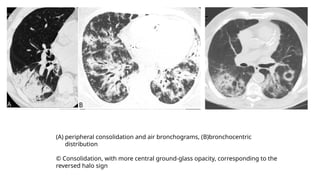

(A) peripheral consolidation and air bronchograms, (B)bronchocentric

distribution

© Consolidation, with more central ground-glass opacity, corresponding to the

reversed halo sign

(A) peripheral consolidationand air bronchograms, (B)bronchocentric distribution © Consolidation, with more central ground-glass opacity, corresponding to the reversed halo sign